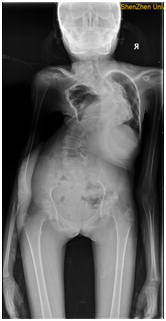

8ff30dd6221d48585f5adc29af38b88.png

鄒女士手術(shù)前影像圖